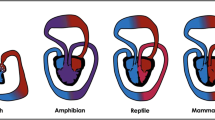

Using animal models of pressure overload stress, we and others have shown that the two ventricles exhibit similar molecular alterations in genes regulating extracellular matrix and cytoskeletal remodeling. However, there are important differences in genes regulating reactive oxygen species (ROS) production and antioxidant protection, angiogenesis, energy production and mitochondrial function (Table 3.1 and Fig. 3.1) [15,16,17,18]. These results confirm differences at the cellular and molecular level in the mechanisms leading to heart failure between the two ventricles, which are discussed below.

Right ventricular susceptibility to heart failure. Stable LVH is characterized by an increase in antioxidant enzymes and angiogenesis and decreased ROS generation, which protects the LV from early progression to heart failure. However in RVH, there is an early decrease in antioxidant enzymes and failure of angiogenesis along with increased ROS and cell death thereby making the RV more susceptible to early heart failure. LVH left ventricular hypertrophy, RVH right ventricular hypertrophy, PS pulmonary stenosis, ROS reactive oxygen species. Cardiac illustrations by Mingming Zhao. With permission from Reddy S, Bernstein D. The vulnerable right ventricle. Current opinion in pediatrics. 2015 Oct;27 (5):563–8 © Wolters Kluwer Health 2015 [18]